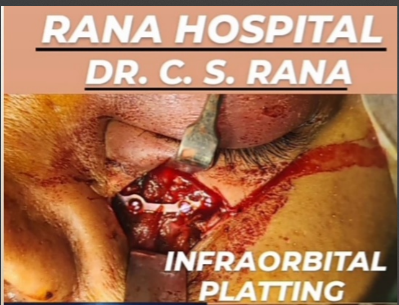

Platting